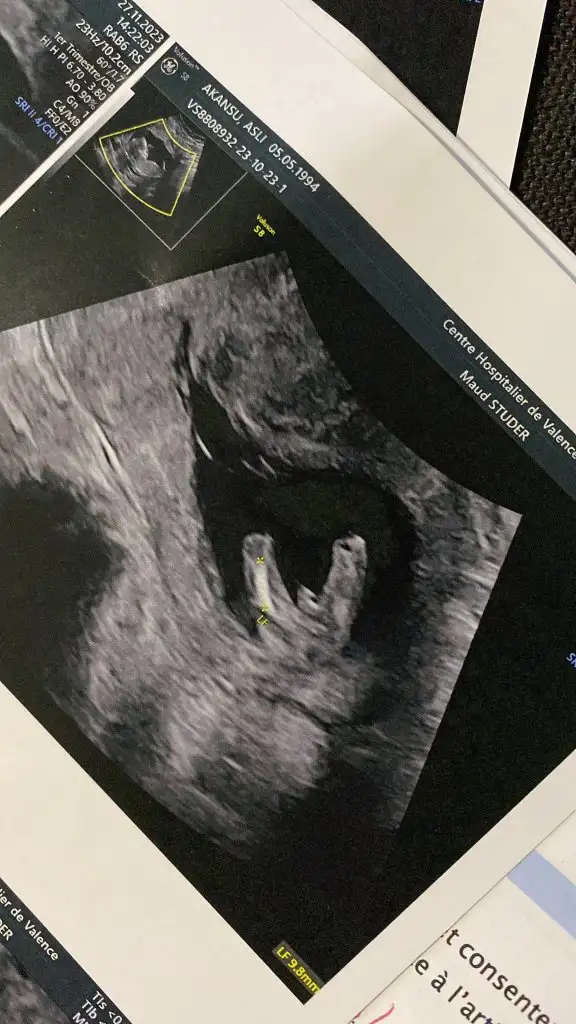

KizBanada tahmin yapar mısınız 13+3

Sizin çok erken ama bazı teorilere göre tahmin yapanlar varmış plesantanin sagindaysa erkek solindaysa kız gibi bilsem yapardimMerhaba bana da yorum yapar mısınız lütfennn vajinal bakıldı 6+3 te